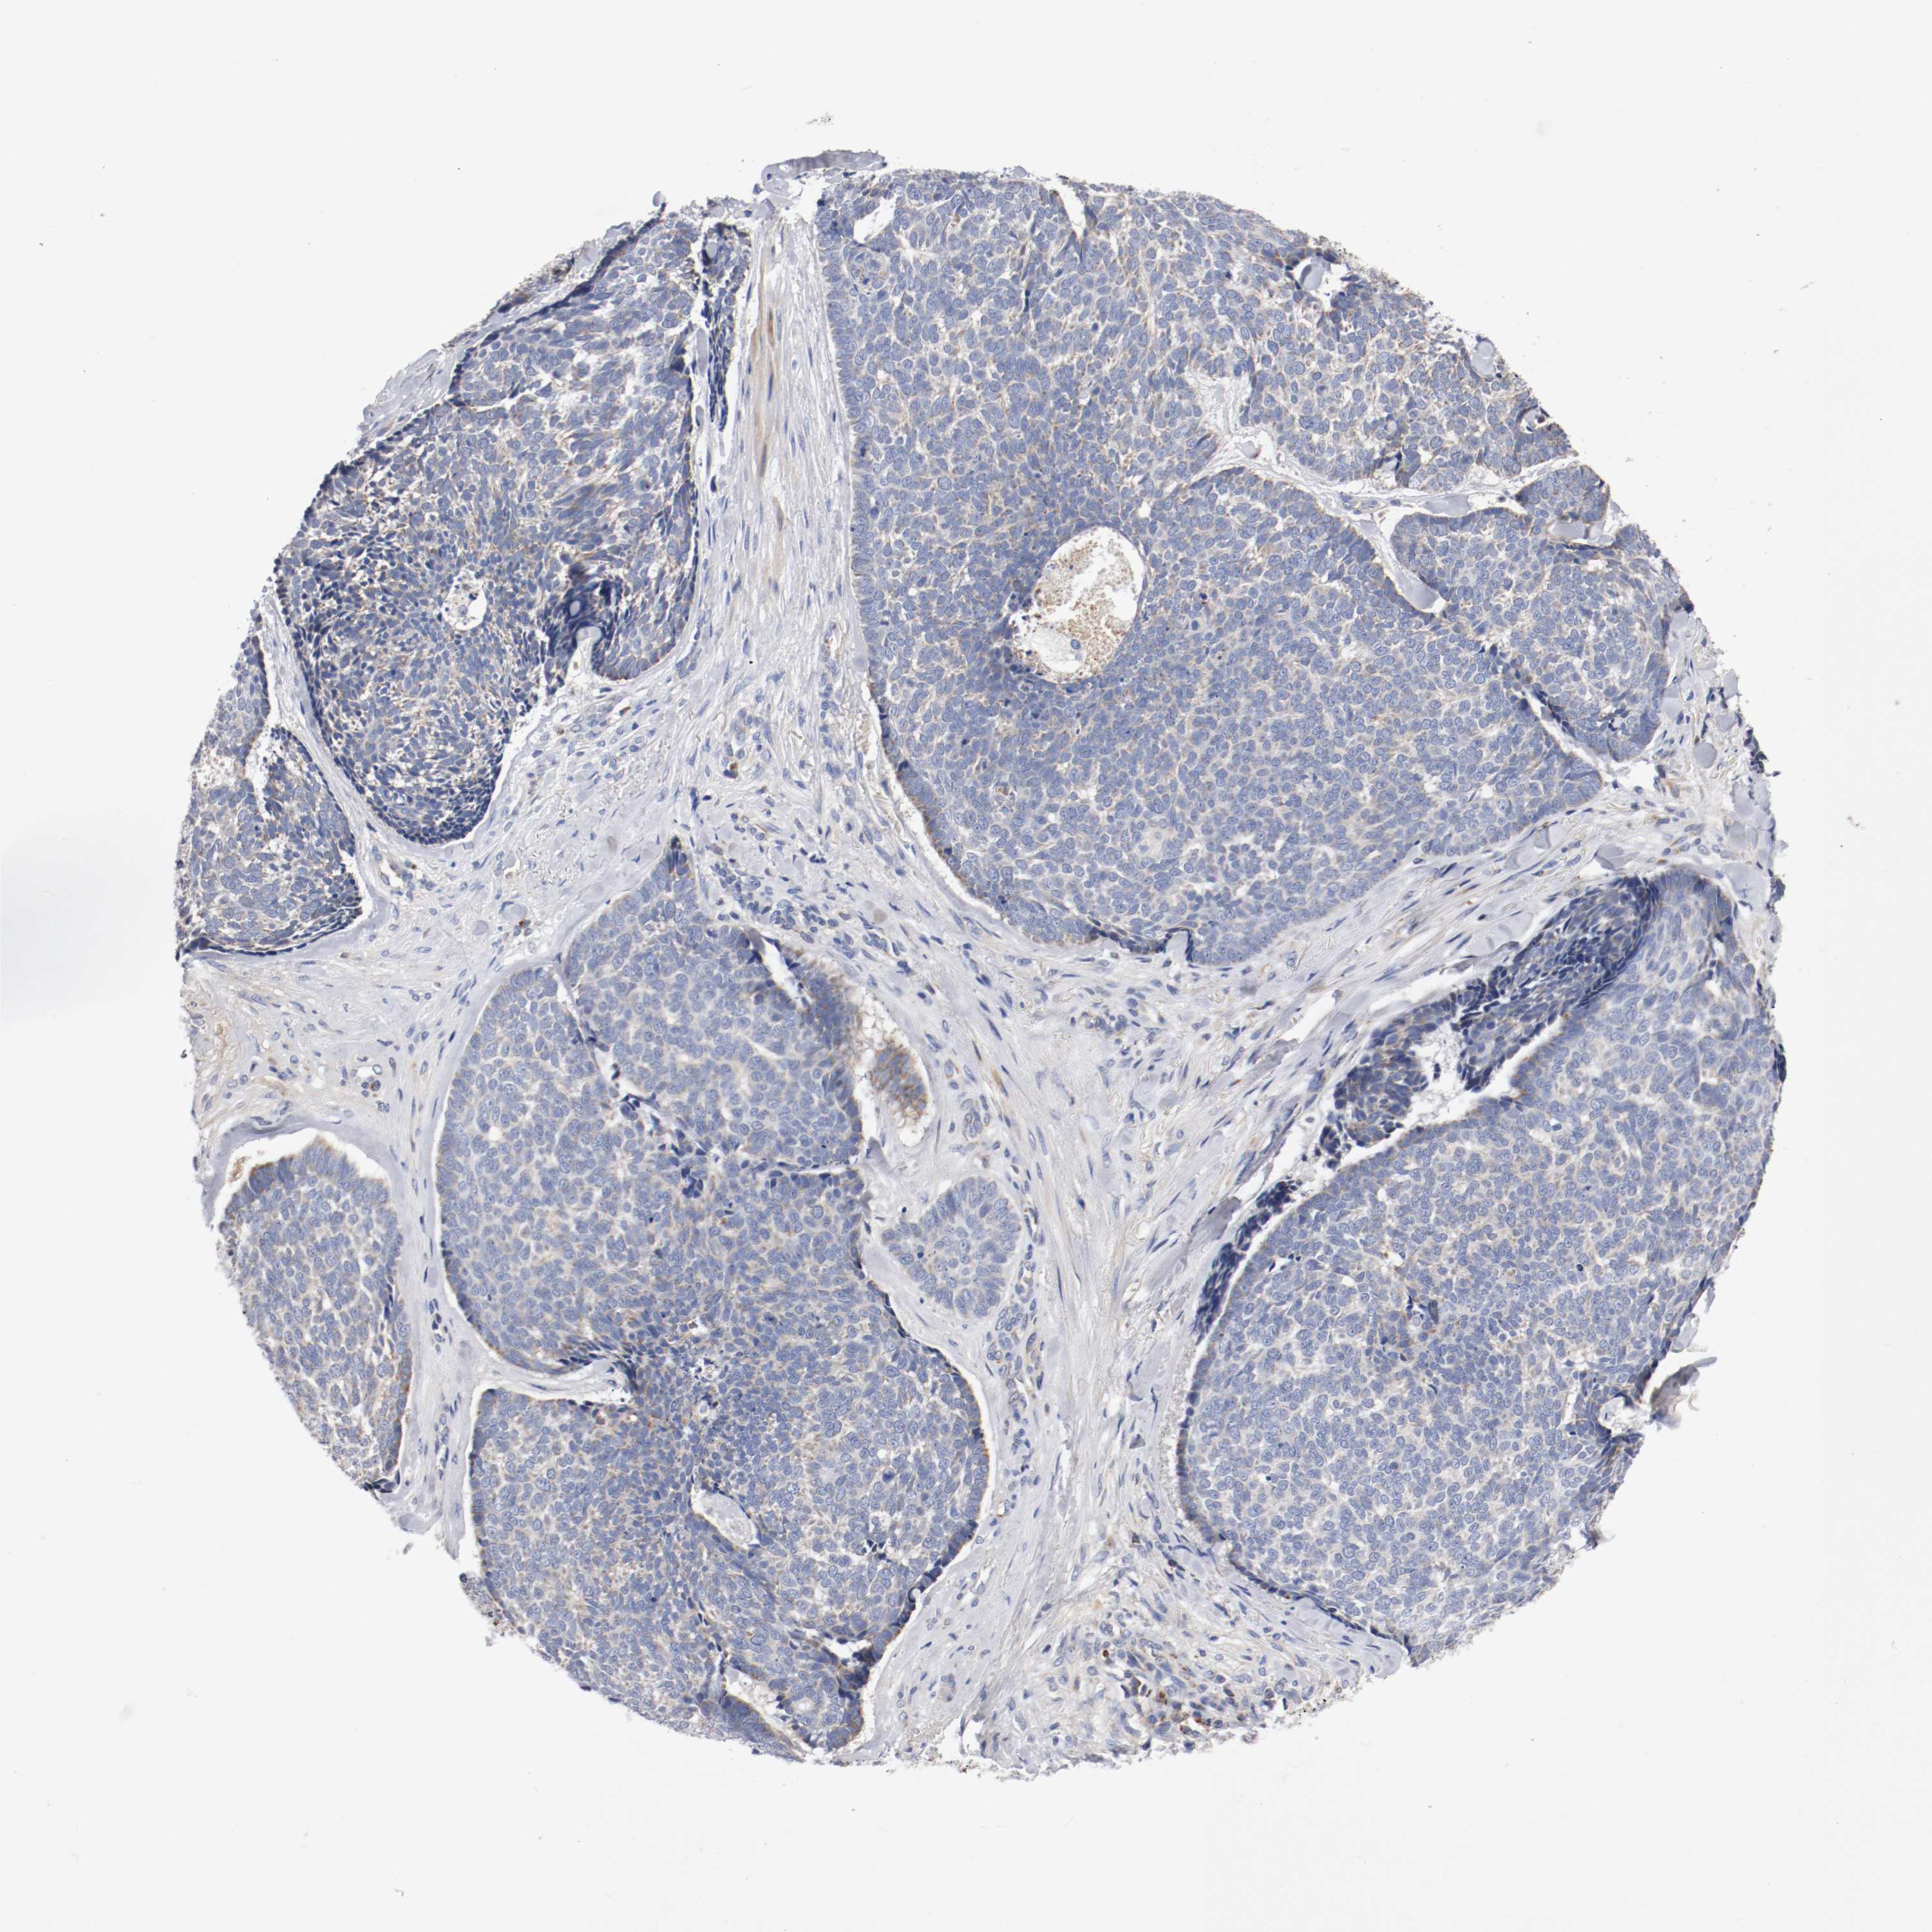

CANCER SKIN CANCER Show tissue menu

Basal cell and squamous cell cancer

SKIN CANCER - Protein expressioni

A mouse-over function shows sample information and annotation data. Click on an image to view it in a full screen mode. Samples can be filtered based on level of antibody staining by selecting one or several of the following categories: high, medium, low and not detected. The assay and annotation is described here.

Each image is clickable and will lead to virtual microscopy that enables deeper exploration of all samples and also displays staining intensity scores, fraction scores and subcellular localization as well as patient and tissue information for each sample.

Antibody HPA004774

Staining

High

Medium

Low

Not detected

Intensity

Strong

Moderate

Weak

Negative

Quantity

>75%

75%-25%

<25%

None

Location

Nuclear

Cytoplasmic/membranous

Cytoplasmic/membranous,nuclear

Squamous cell carcinoma, NOS

Basal cell carcinoma